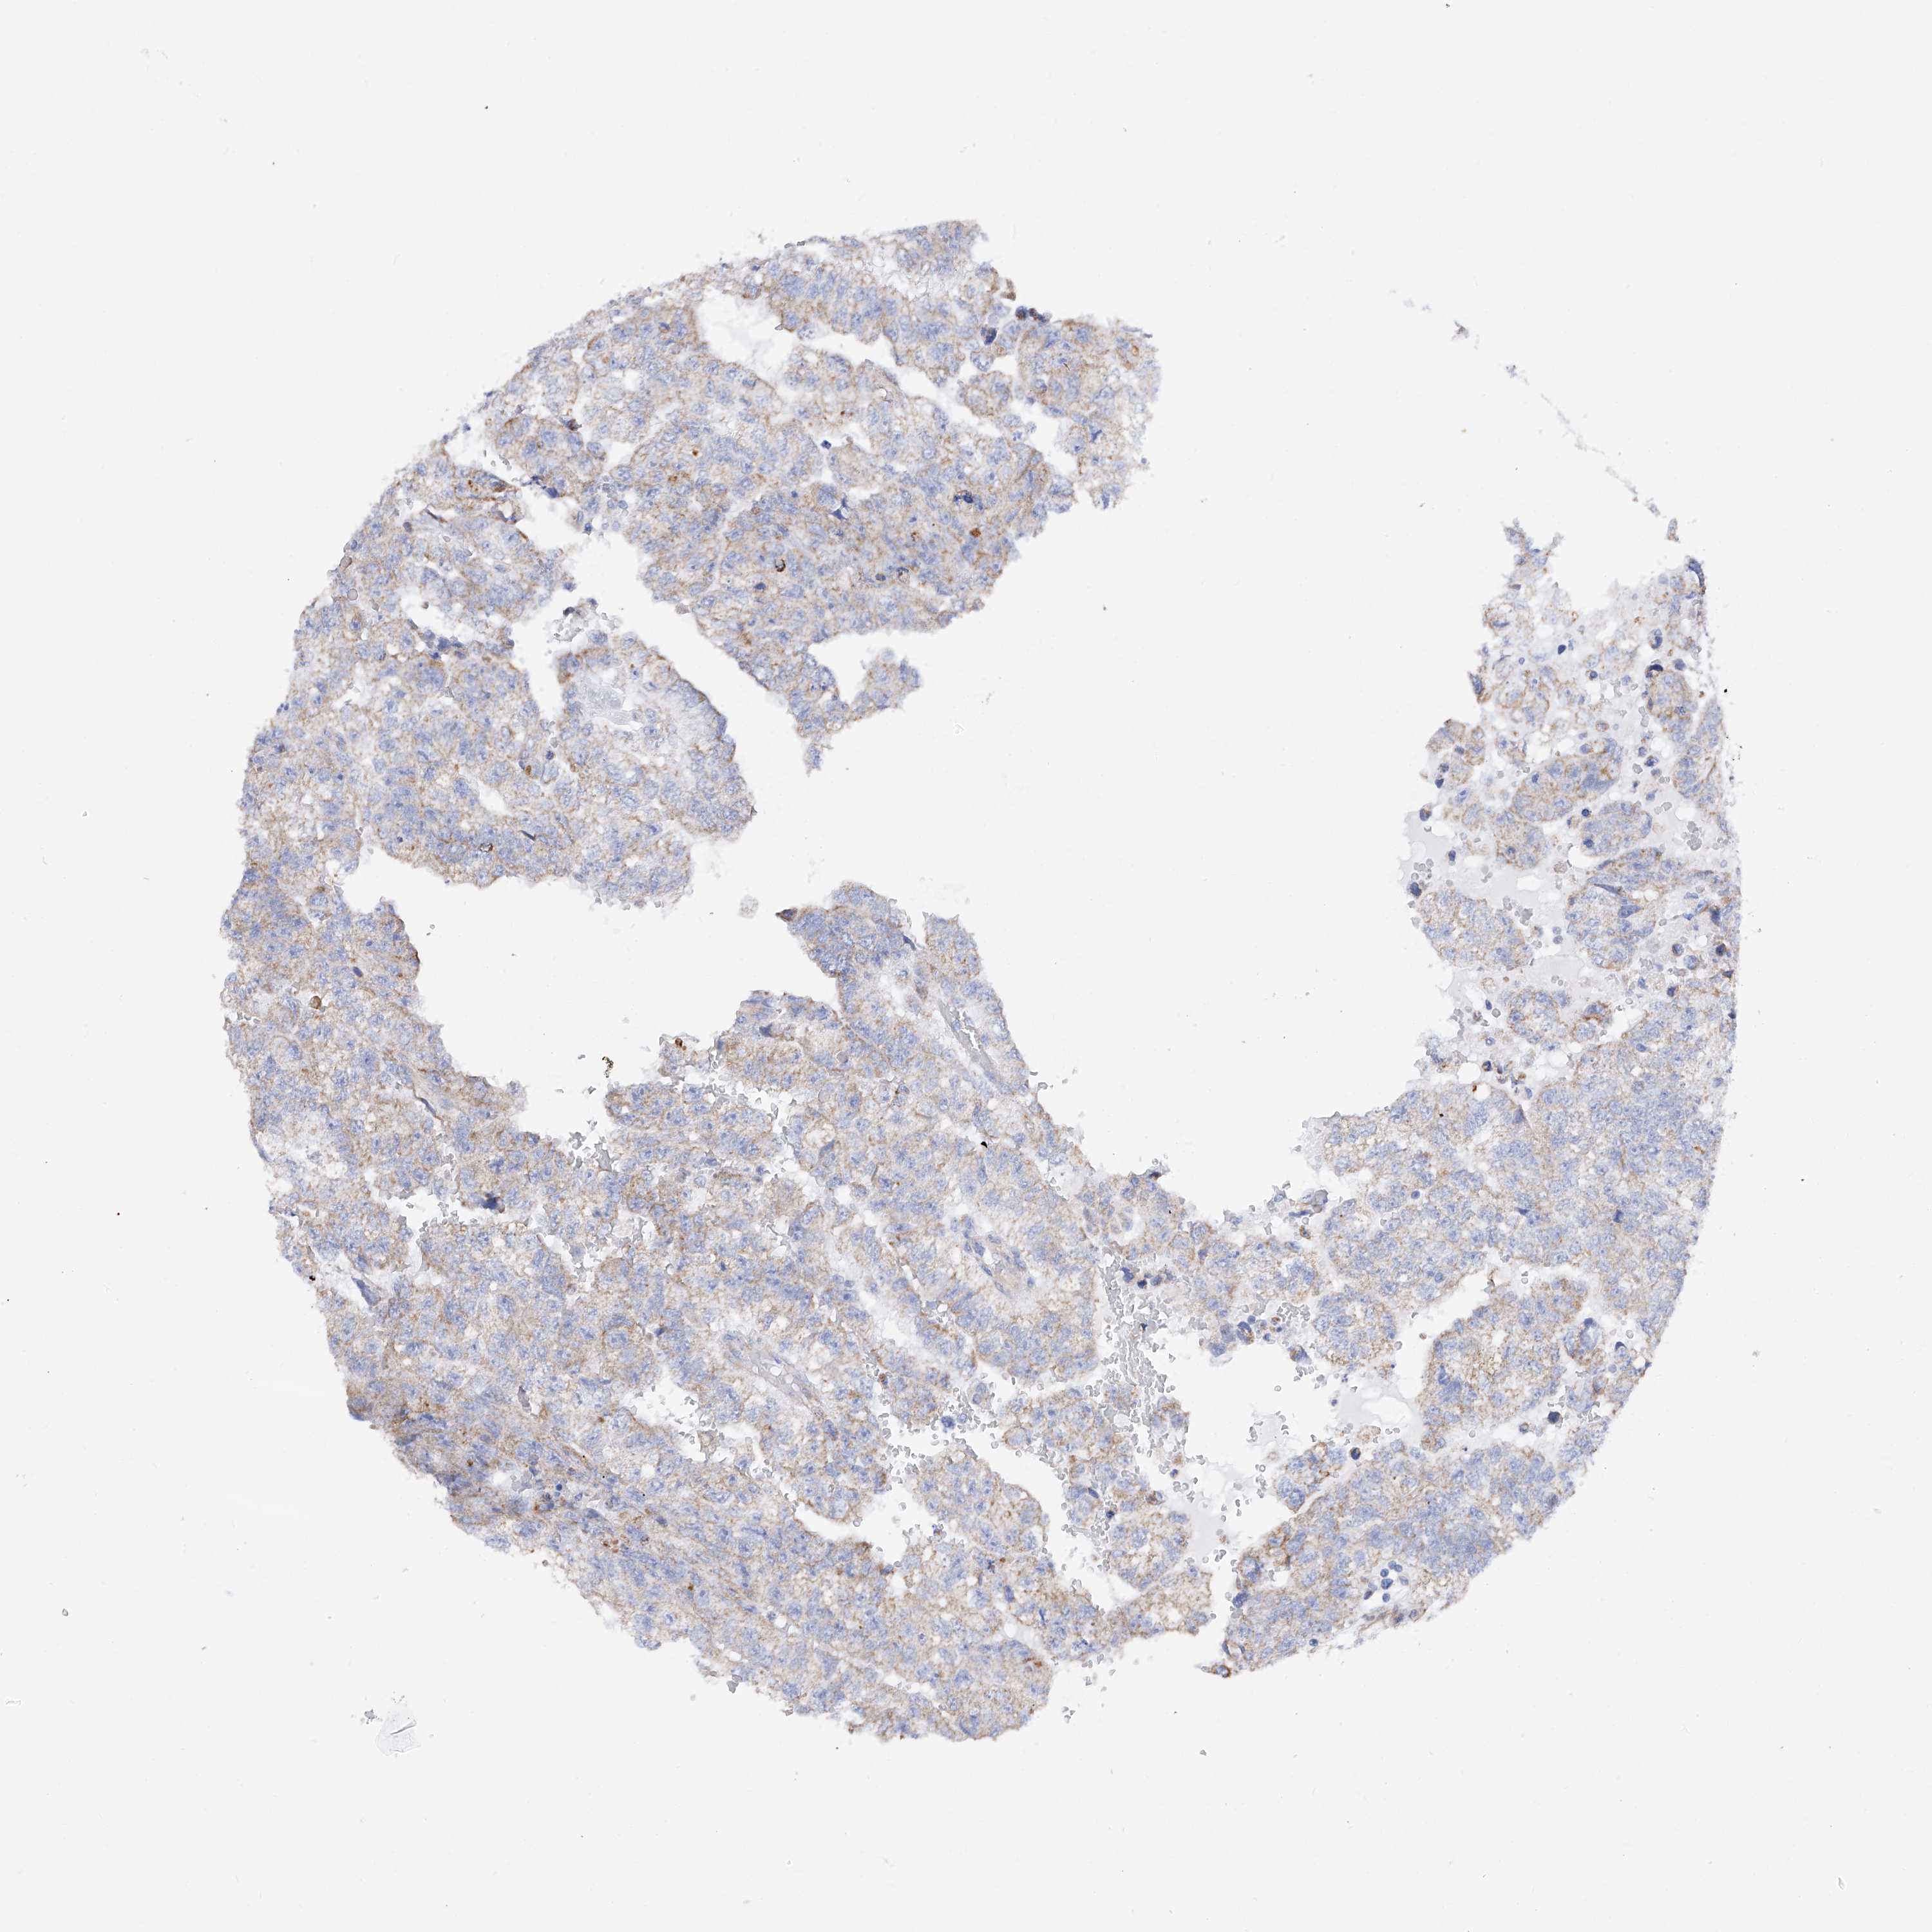

TESTIS CANCER - Protein expressioni

A mouse-over function shows sample information and annotation data. Click on an image to view it in a full screen mode. Samples can be filtered based on level of antibody staining by selecting one or several of the following categories: high, medium, low and not detected. The assay and annotation is described here.

Note that samples used for immunohistochemistry by the Human Protein Atlas do not correspond to samples in the TCGA dataset.

Antibody stainingi

Antibody staining in the annotated cell types in the current human tissue is reported as not detected, low, medium, or high, based on conventional immunohistochemistry profiling in selected tissues. This score is based on the combination of the staining intensity and fraction of stained cells.

Each image is clickable and will lead to virtual microscopy that enables deeper exploration of all samples and also displays staining intensity scores, fraction scores and subcellular localization as well as patient and tissue information for each sample.

Antibody HPA030188

Antibody HPA030189

Antibody CAB002210

Carcinoma, Embryonal, NOS

Seminoma, NOS